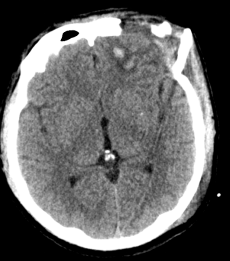

左额骨骨质缺损,额叶脑出血、挫裂伤